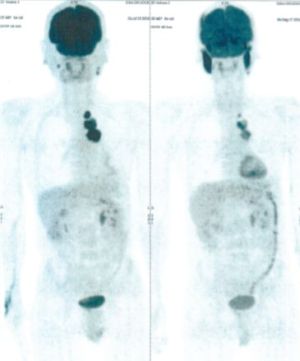

CASE NO: 2 (HEPATOCELLULAR CARCINOMA)

A 40+ man with hepatocellular carcinoma, an incurable cancer. After 2 treatment, the activity of the hepatocellular carcinoma is less.

CASE NO: 2 (HEPATOCELLULAR CARCINOMA) - After a few more treatments

After another few treatment, the activity of the hepatocellular carcinoma is much less. The patient never came back for further treatment, but this case, and case no: 1, shows that incurable hepatocellular carcinoma, often seen in hepatitis B and C patients, can be cured.